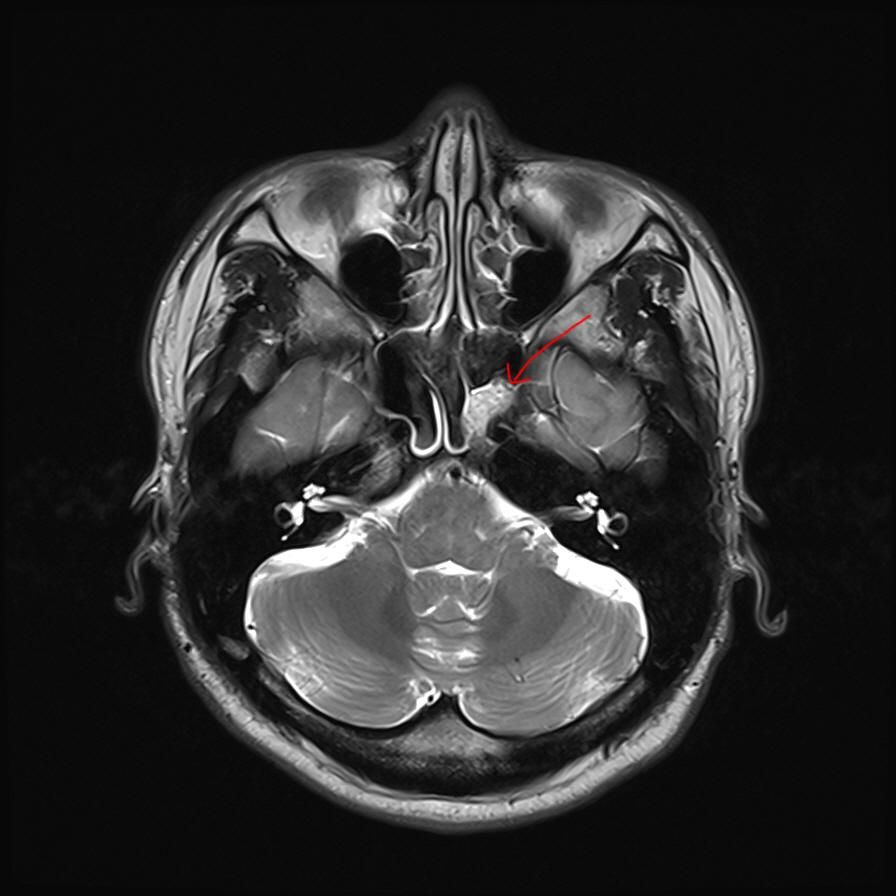

mri 사진을 봤을 때 정확히 어디가 막힌 걸까요? 그리고 치료는 할 수 있는 걸까요???

• 4번 째 사진

올려주신 영상 관련 보다 더 자세한 분석 원하시면 영상의학과 전문의한테 물어보셔야 해요

말씀하신 증상 관련 답변 드리자면 15년동안 지속된 귀와 코 사이 막힘 증상은 이관(유스타키오관) 기능 장애일 가능성이 높습니다. 진한 콧물을 강하게 들이마신 후부터 증상이 생겼다면, 이관이 분비물이나 압력 변화로 막히거나 손상되었을 가능성이 있습니다. 이관은 코 뒤쪽과 귀 중이를 연결하는 통로로, 막히면 귀먹먹함, 압력감, 울림 증상 등이 지속될 수 있습니다. MRI나 CT를 통해 이관 주변 구조(비인두, 부비동, 중이강 등)의 해부학적 이상을 더 정확히 확인해야 합니다.